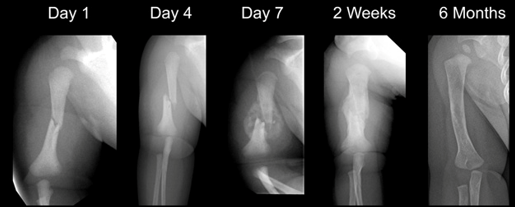

Bone Healing and Remodeling

Stages of Bone Healing

Inflammatory Phase:

Duration: hours to days

A hematoma forms, then begins forming a primary callus.

Reparative Phase:

Duration: days to weeks

A thick mass of callus forms around the bone ends.

New bone is formed from bone-forming cells.

Remodeling Phase:

Duration: months to years

The callus becomes smoother and is calcified.